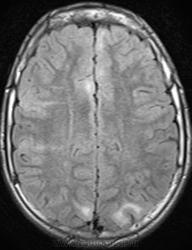

Это болезнь Бурневилля - одна из форм факоматозов?

Да, это болезнь Бурневилля-Прингла, один из видов факоматоза. Врожденное заболевание, развивается из-за нарушений в одной из хромосом.

да спасибо за случай,получается что первыми заподозрили офтальмлоги?